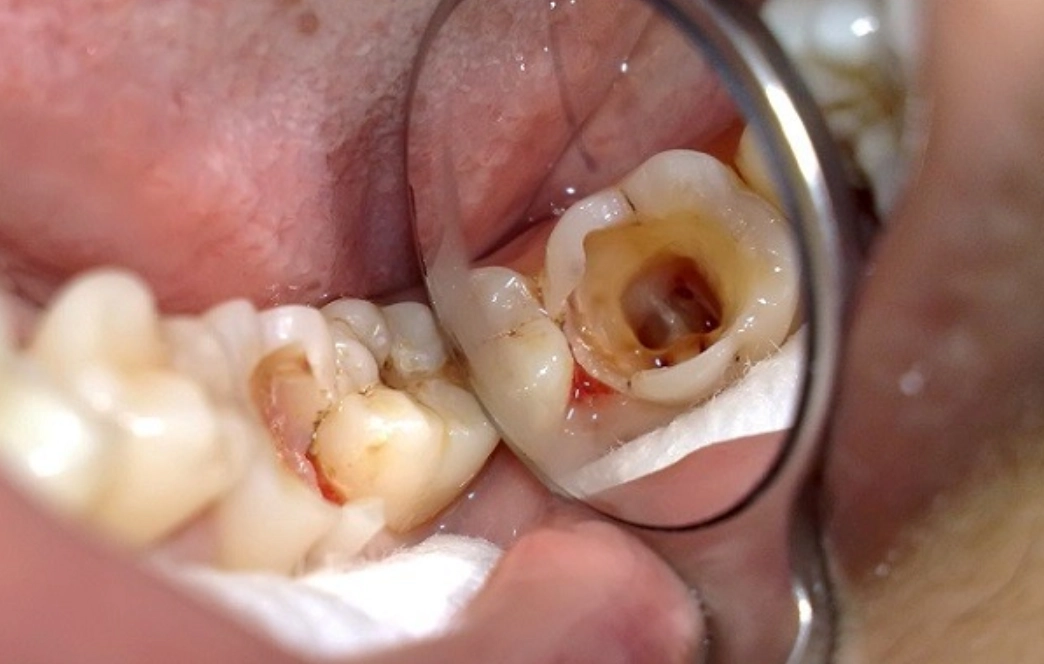

Răng bị sâu nặng, vi khuẩn đã tấn công vào buồng tủy: Khi lỗ sâu đã phá hủy lớp men và ngà răng, tấn công vào buồng tủy, nó sẽ gây ra tình trạng viêm tủy cấp với các triệu chứng như đau nhức dữ dội, buốt ê ẩm khi ăn đồ nóng lạnh. Lúc này, việc lấy tủy là bắt buộc để loại bỏ hoàn toàn ổ viêm trước khi bọc sứ.